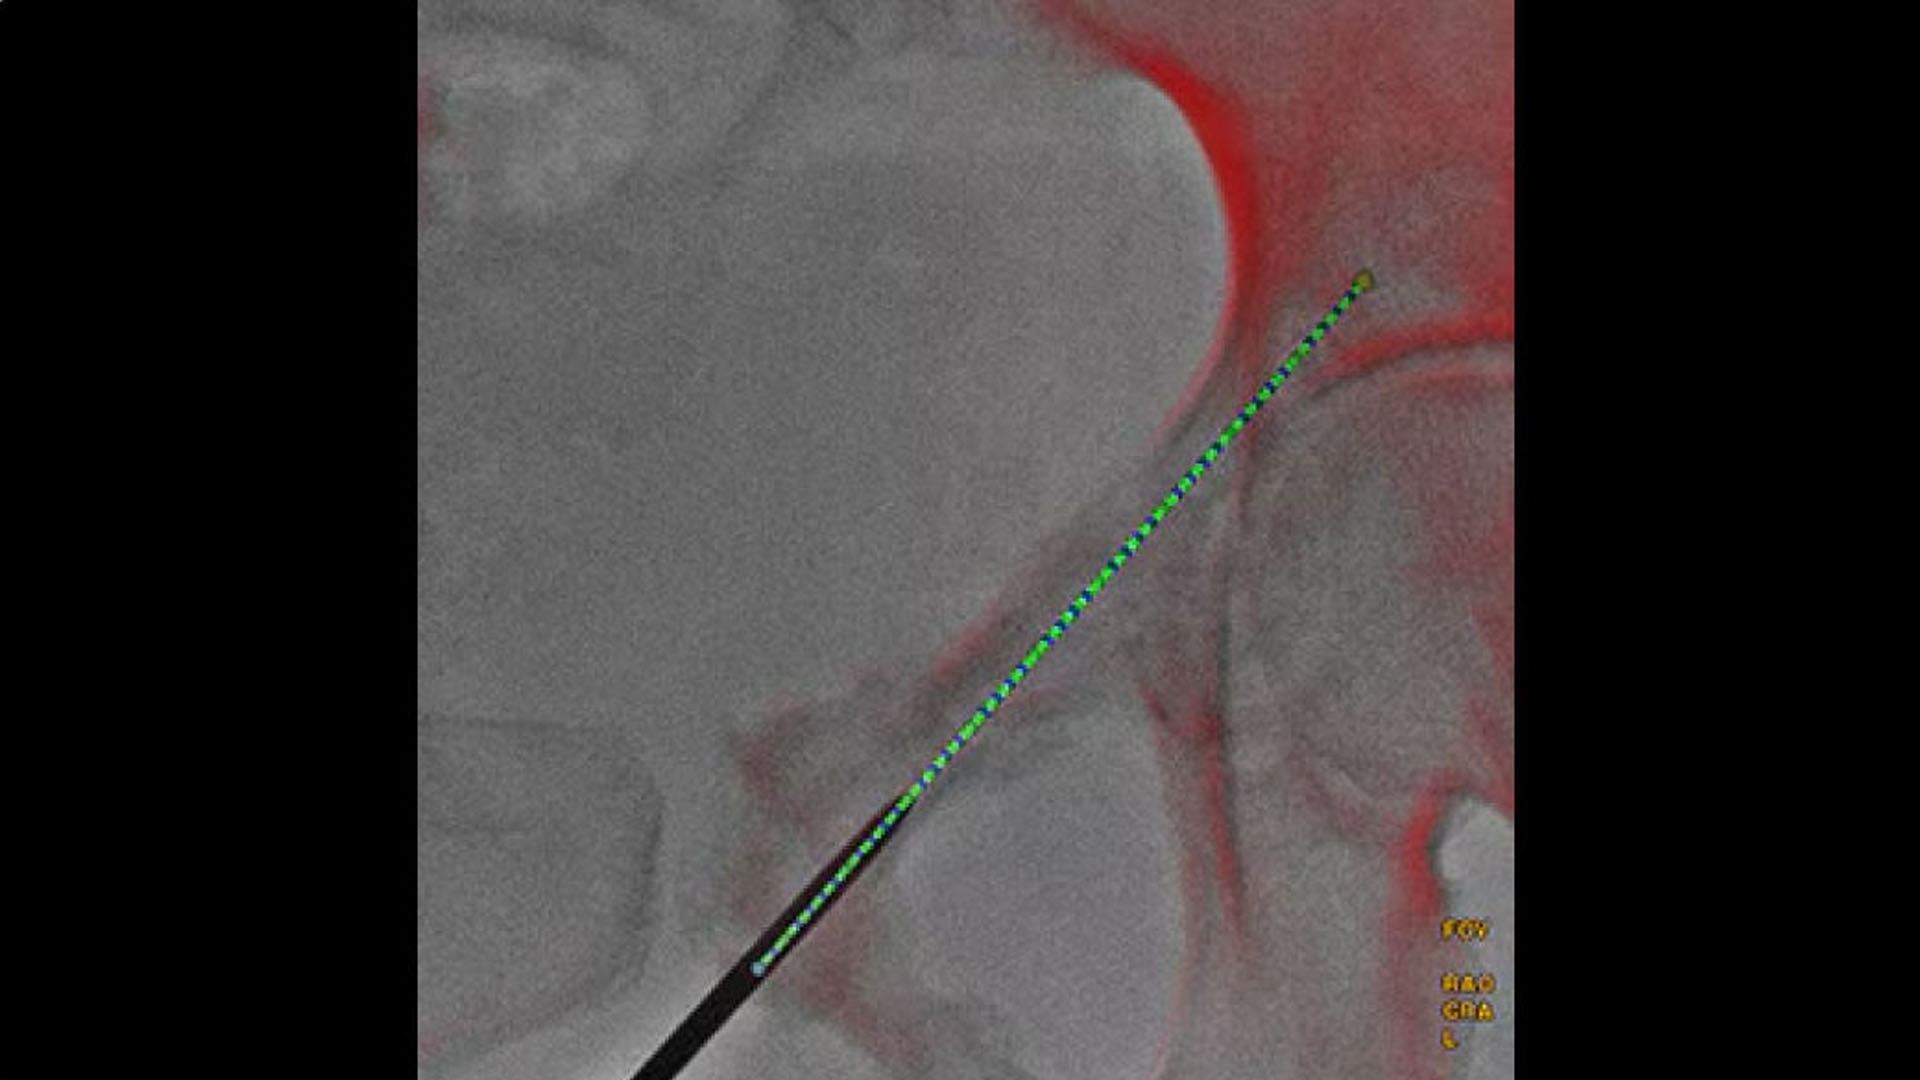

Real-time visualization

Provide real-time visualization of needle positions in the 3D space

Improve outcomes

Helps improve accuracy and reduce dose during needle interventions